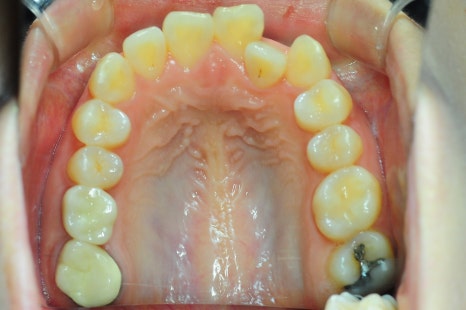

"입이 나와 보여요"라며 찾아주신 여성 환자분이셨는데요.

치료 전 X-ray 측면 모습으로도 치아가 앞으로 기울어져 있고,

입이 튀어나온 모습을 확인할 수 있습니다.

상악, 하악 각각 첫 번째 소구치를 발치했고,

인비절라인을 통해 치아를 뒤로 이동시키며 돌출을 점진적으로 개선했습니다.

뻐드러져 있던 치아 배열 모습이 정상적으로 돌아온 걸 확인하실 수 있을 겁니다.